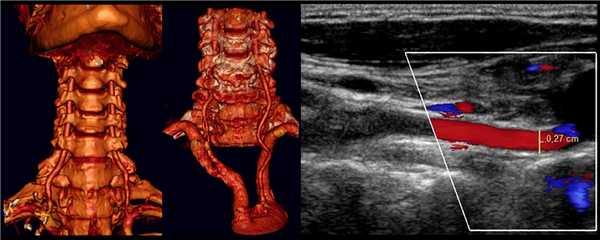

КИМ составляют интима и медиа сосудистой стенки. Адвентиция сливается с окружающими тканями. Измеряют КИМ ОСА и ВСА на 1 см ниже и выше бифуркации.

КИМ лучше видно на удаленной стенке — анэхогенная медиа между гиперэхогенной интимой и адвентицией. В норме 0,5-0,8 мм, у пожилых 1,0-1,1 мм.

В М-режиме диаметр сосуда измеряют между интимой и адвентицией в систолу и диастолу.

ПА сканируют продольно кнутри от кивательной мышцы, от угла нижней челюсти до верхнего края ключицы.

Для ПА характерна асимметрия, обычно левая больше правой. Когда ПА менее 2 мм, можно говорить о гипоплазии.

Для исследования I сегмента ПА датчик смещают до ключицы. В норме ПА отходит от ПКА на уровне С7 и входит в костный канал на уровне С6.

II сегмент ПА имеет прерывистый вид, т.к. проходит в костном канале поперечных отростков С6-С2 и на месте поперечных отростков акустическое затенение.